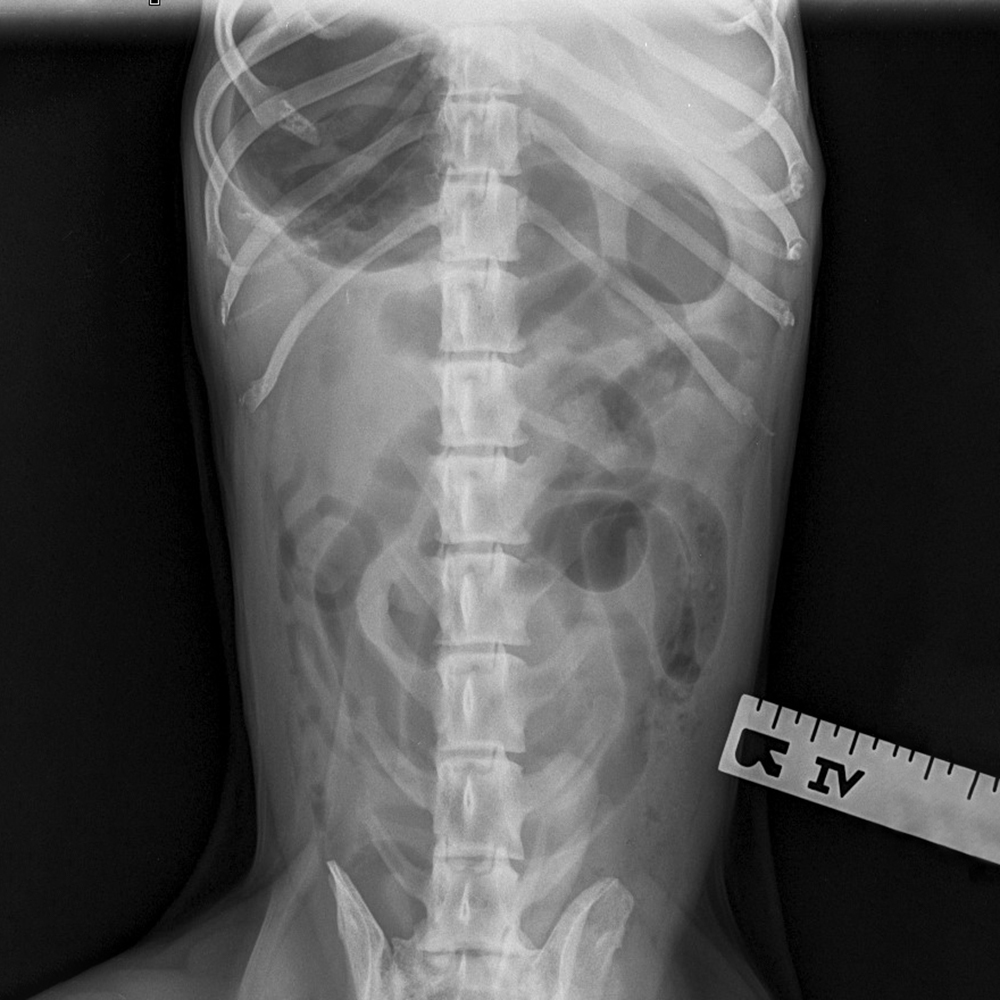

Abdominal radiographs were taken as thoughts turned to a possible ingested foreign body. X-rays can highlight a lot of things but some objects are radiolucent, meaning the x-ray beam passes through, hiding their presence. Although Peppy’s radiograph didn’t show an obvious foreign body there were some clues such as the dilated loops of intestines. Peppy was taken to theatre for exploratory abdominal surgery where a large piece of tennis ball was located and removed from a section of small intestine.